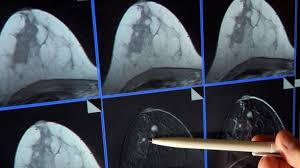

Hält der Husten jedoch acht Wochen oder länger an sollte die Ursache in weiteren Untersuchungen abgeklärt werden rät Kardos. Mithilfe von Lungenfunktionstests und Röntgenaufnahmen können ernsthafte Erkrankungen wie ein Tumor oder eine chronisch-obstruktive Lungenerkrankung COPD erkannt beziehungsweise ausgeschlossen werden. Viele Patienten mit COPD oder anderen Lungenproblemen wie Athma haben mit lätigem Huten zu kämpfen der einfach nicht zu verchwinden cheint. Im Gegenzug bedeutet nicht jeder Husten sofort Krebs. Lähmungen starke Schmerzen Bluthusten sowie Gewichtsverlust und Schwäche zählen ebenfalls zu den Warnzeichen die abgeklärt werden sollten. Erst in weiter fortgeschrittenen Stadien löst Lungenkrebs Symptome wie blutigen Auswurf Atemnot und rapiden Gewichtsverlust aus. Gereizte Atemwege nach Erkältung oder Grippe. Es kann Ursache Kopfschmerzen Schwindel Schwitzen Appetitlosigkeit und Schlafverlust. Welche Symptome zusätzlich bei Lungenkrebs auftreten könnten und welche anderen Krankheiten sich mit trockenem Husten zeigen könnten wird in folgendem Text erklärt.